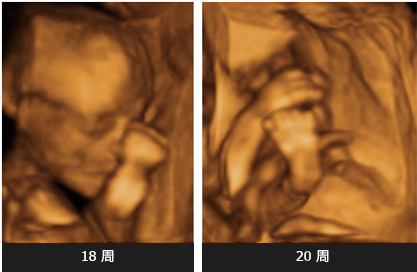

目前的超声诊断仪越来越先进。早期的超声诊断仪可以看到胎儿的二维图像(长度和宽度),或根据发出的声波生成横截面图像,每次能看到一个平面图。虽然得到的图像提供了非常有用的信息,但图像看上去不像胎儿。然而对于现代超声诊断仪,它采用数字化探头,能够收集到累积折射出来的声波量,形成具有厚度的三维立体图像,使胎儿的图像看上去更加逼真。现代的四维超声诊断仪可以保存每一幅三维图像,并连续的显示出来,形成如同实况发生的运动图像,即实时动态图像。通过四维超声诊断技术,我们能清晰地对胎儿行为进行研究。

孕期的任何胎龄阶段都可进行四维彩超检查,但不同胎龄阶段得到的图像效果不同。在孕早期,能看到胎儿的全身图像。在胎龄更大时进行检查,由于胎儿身体的各个器官得到了进一步发育,我们能看到更详尽的信息。若在胎龄35周以上进行检查,脸部可能无法清晰可见,因为胎儿头部朝下并开始落入盆腔。然而,即使在小于32周的胎龄进行检查,如果腹中胎儿在整个检查过程都保持背朝前的姿势,也可能无法看清脸部。因此,建议在胎龄不超过26周时进行检查效果最好。